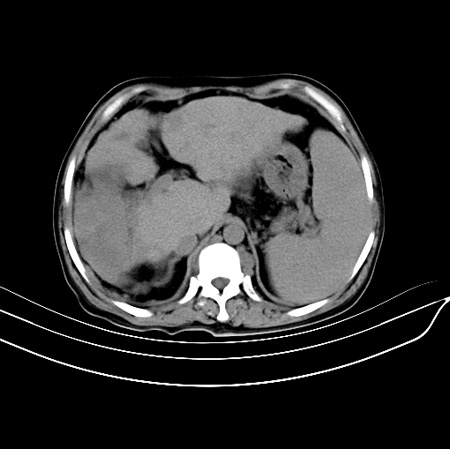

以下是引用江尾海头在2007-9-7 19:01:00的发言:[br]肝叶比例失调,肝边缘高低不平,尾状叶增大,肝裂增宽。肝右叶见较大密度减低影,边缘欠清。脾脏明显增大,胃底及奇静脉半奇静脉曲张。胆囊未见明显显示。 考虑:1、肝癌。2、肝硬化伴脾大静脉曲张。

以下是引用zhangxu5888在2007-9-7 22:31:00的发言:[br]1、肝硬化,食管 胃底及奇静脉半奇静脉曲张;2、脾脏肿大; 3、肝右叶的病灶呈锲性改变,内可见条片状钙化,边界清晰,密度明显低于周围正常肝组织,我觉得肝癌可能性不是很大, 同意楼上观点,有可能是栓塞,建议增强.